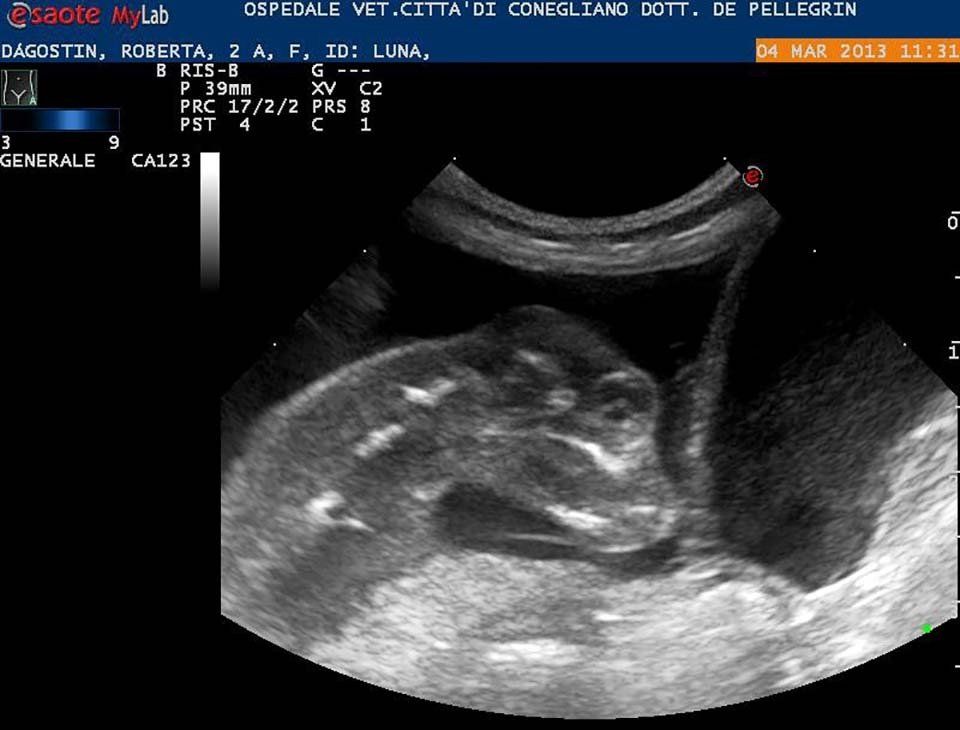

Tra i servizi che l’Ospedale Veterinario Città di Conegliano fornisce, non mancano quelli di diagnostica per immagini:

ecografia, radiologia digitale, TC.

Gli specialisti Roberto De Pellegrin e Riccardo Pelizzon, in particolare, si occupano degli esami ecografici, ecocardiografici, tomografici per l'acquisizione di immagini del corpo del paziente attraverso l'esposizione a ultrasuoni o a raggi X.

Si tratta di esami non invasivi né dolorosi, che possono essere eseguiti molto rapidamente.